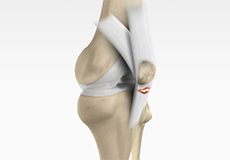

Posterolateral Corner (PLC) Reconstruction

Posterolateral corner injury is damage or injury to the structures of the posterolateral corner. The structures of the posterolateral corner include the lateral collateral ligament, the popliteus tendon, and the popliteo-fibular ligament. Injuries to the posterolateral corner most often occur with athletic trauma, motor-vehicle accidents, and falls.